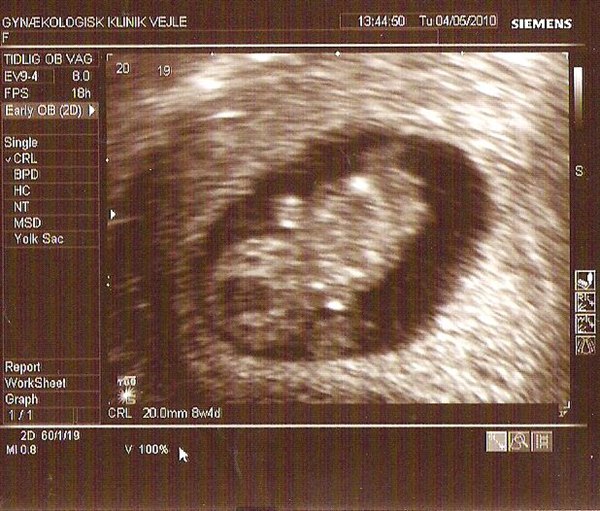

Hold da op, ja så kan jeg godt forstå de har sendt dig til scanning. Dejligt at der var liv! Hvordan har du det nu?

Har det rigtig godt, blødte lidt i går, men det var så lidt så det ikke har slået mig ud af kurs, men er meget obs på hvad kroppen sender af signaler. Var til nf ionsdags, men da den lille ikke ville vende rigtig efter utrolig mange forsøg så fik jeg en ny tid til på torsdag igen.